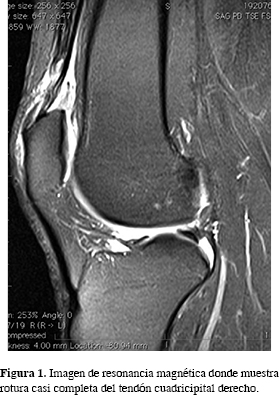

El estudio mediante resonancia magnética mostró una evidencia objetiva de discontinuidad de fibras tendinosas de forma completa en el tendón cuadricipital izquierdo, con una discontinuidad casi completa en el lado derecho (Figuras 1 y 2).

El diagnóstico fue de rotura completa del tendón cuadricipital en la rodilla izquierda y de parcial (más de 80% de las fibras) en la derecha.